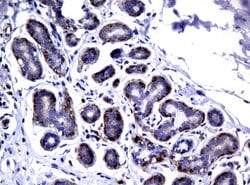

DEF6 Mouse anti-Human, Clone: UMAB51, liquid, UltraMAB™

DEF6, or IBP, is a guanine nucleotide exchange factor for RAC and CDC42 that is highly expressed in B and T cells.Specifications

| Immunohistochemistry (Paraffin), Western Blot | |